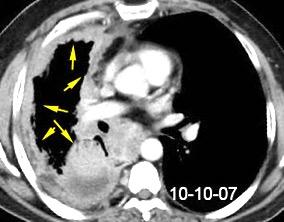

40. EMPIEMA PLEURAL. ORIGEN HEPÁTICO